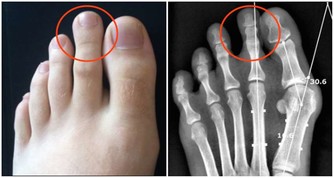

這種坐姿影響跳躍、投擲和踢腿等動作。當小孩以「W型坐姿」坐在地上時,膝蓋是向外翻,這種姿勢會導致孩子的髖外展肌、股後肌群、內轉肌和跟腱承受更大的壓力,還會影響孩子背部及盆骨的發育,導致孩子形成內八。

更糟的是,很多專家認為這種坐姿與發育遲緩有一定的聯繫。這種看似舒服的姿勢會給髖外展肌 (hip abductors)、股後肌群 (hamstrings)、內轉肌 (internal rotators)、跟腱 (heel cords)帶來額外的壓力,長時間以這種方式坐著,雙腳可能會內撇和足弓反轉,影響步行姿勢,嚴重更會引致「脊柱前凸」,即脊柱大幅向內彎曲,影響身體整體的平衡感和協調能力。最終你可能不得不去醫院看骨科。